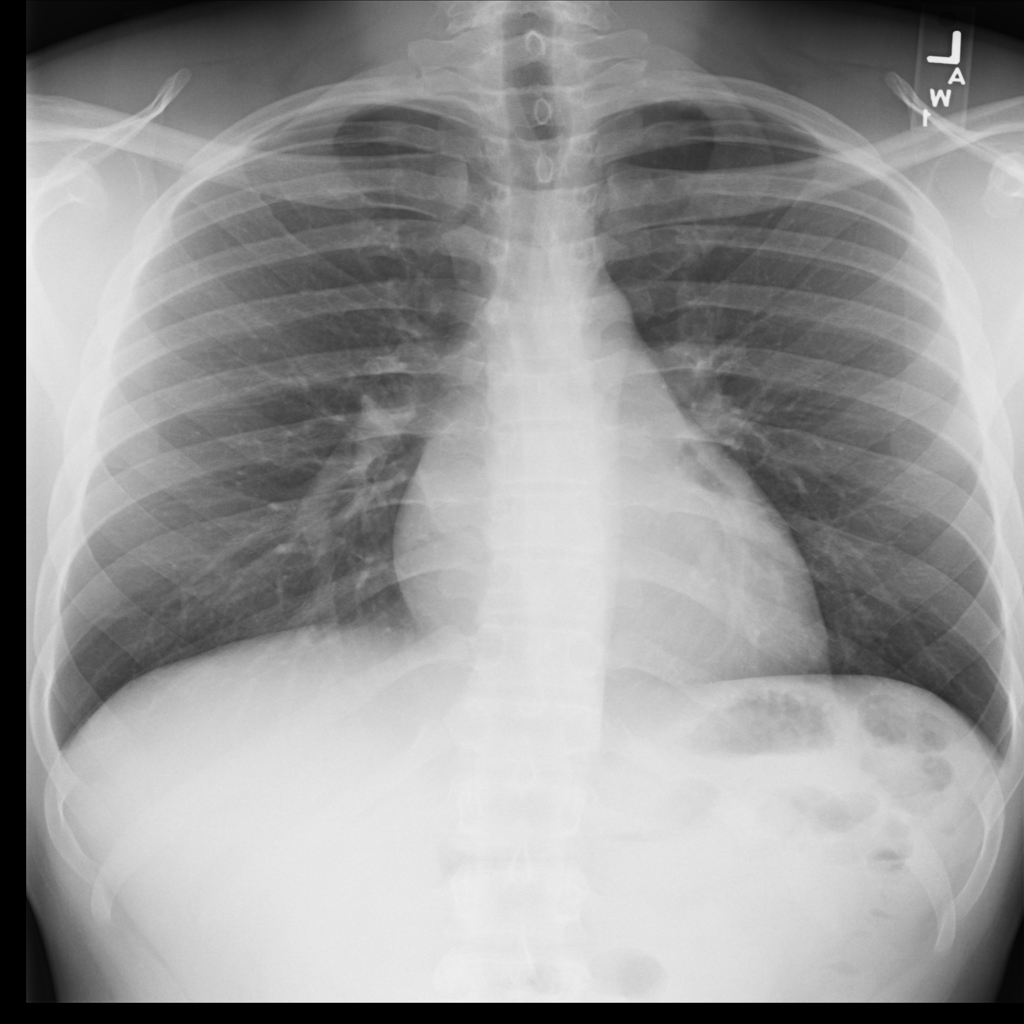

PAT-C0E5 · IMG-015Pneumonia

PAT-C0E5 · IMG-015

AP